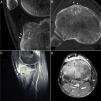

Sagittal (A) and axial (B) computed tomography images of right knee showing an osteolytic lesion in the subendosteal region of the anterior tibial tuberosity, with a “nidus” formed by ossified matrix, compatible with osteoid osteoma (arrow), encircled by extensive sclerosis of the surrounding medullary bone (asterisks) and a solid periosteal reaction in the adjacent cortical bone (arrowheads). Post-gadolinium sagittal (C) and axial (D) T1-weighted spectral presaturation with inversion recovery (STIR) magnetic resonance images revealed perilesional contrast uptake in the form of a ring (arrow), and in surrounding bone edema (asterisks) and Hoffa fat pad (arrowheads).

A 15-year-old boy presented with an 8-month history of mechanical pain in right knee. It would be intermittent at first and later become continuous, making it difficult for him to walk, and swelling was observed in that area. The treatment consisted of nonsteroidal anti-inflammatory drugs (NSAID), initially ibuprofen, which was replaced by diclofenac, but there was no improvement. He had no history of injury, fever or constitutional symptoms, or manifestations affecting any other peripheral or axial joint or enthesitis. He had been diagnosed with guttate psoriasis at the age of 10 years, with occasional episodes until he was 13, and was treated with topical glucocorticoids; however, he had no family history of psoriasis, psoriatic arthritis, ankylosing spondylitis or inflammatory bowel disease. Physical examination revealed muscle atrophy in distal thigh and swelling in right infrapatellar region, which was warm, and he had a limitation in last few degrees of flexion, but with no signs of joint effusion. The results of laboratory tests, including biochemical analyses, complete blood count and acute-phase reactants (erythrocyte sedimentation rate 6mm/h, C-reactive protein 2.31mg/dL) were normal. Human leukocyte antigen (HLA) typing revealed the presence of Cw6, DR4 and DQ8 haplotypes, but not B27, and the patient was negative for rheumatoid factor and antinuclear antibodies. Plain radiography of the knees showed a sclerotic area in the upper third of right tibia (Fig. 1A and B), which, according to computed tomography (CT), corresponded to an osteolytic lesion measuring 5mm in diameter in anterior tibial tuberosity, with a “nidus” formed by an ossified matrix, compatible with OO (Fig. 2B and C), with extensive sclerosis of the medullary bone and a solid periosteal reaction in the adjacent cortical bone. Magnetic resonance revealed intense contrast uptake in and around the lesion, as well as in the surrounding bone edema and the Hoffa fat pad (Fig. 2C and D). Bone scintigraphy disclosed hyperemia and a focal increase in the osteogenic response in the proximal epiphysis of right tibia, with no other significant changes. The patient underwent CT-guided radiofrequency ablation, and the pain disappeared a few days after the procedure, and he recovered complete mobility 1 month later, although he had mild persistent muscle atrophy.